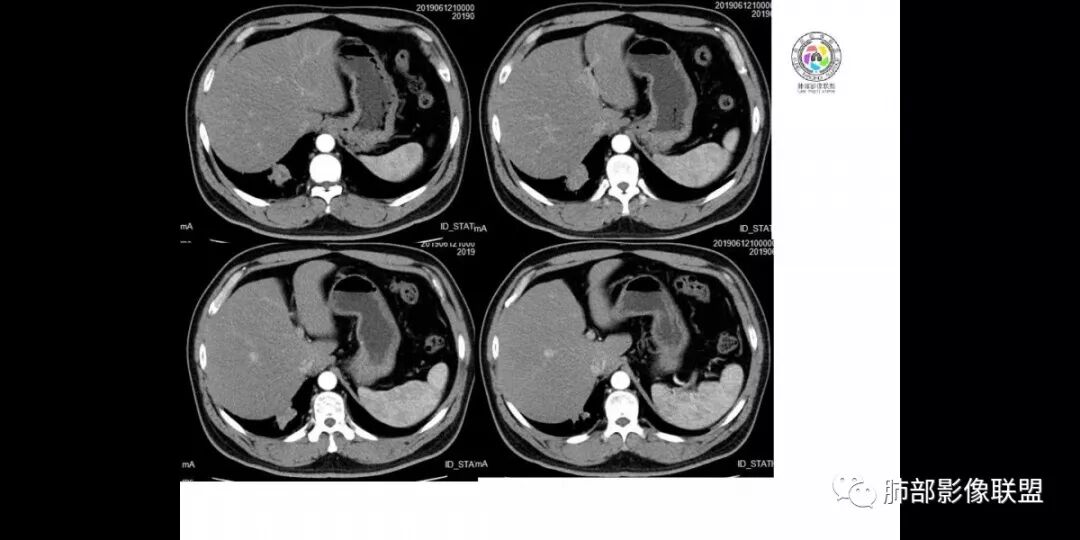

患者男,45岁,因乏力、低热、心悸入院,最高体温38℃,偶有咳嗽、无咳痰、咯血,肿瘤标志物阴性。

影像资料

患者中年男性,以乏力、低热、心悸入院。胸部CT:右肺下叶后基底段近胸膜实性结节灶,病灶周围磨玻璃模糊影,可见短毛刺,边缘呈刀切、平直,冠状位肺窗病灶与膈胸膜呈宽基地,纵隔窗可见病灶内空洞及低密度区,增强明显强化及延迟强化,综合考虑良性感染性病变。肺隐球菌病可能大,机化性肺炎、腺癌次之,结核待排。

右肺下叶后基底段结节,边缘较清,有浅分叶,病灶长轴与胸膜平形,以平直收缩为主,局部稍膨隆,有长短不一的毛刺,边缘模糊,周围有小片状模糊hggo,中心有小空泡或小空 洞,内壁光整,增强后延迟强化,提示会不会有纤维组织成份,而且空腔内壁强化明显且完整,邻近胸膜有糊墙,考虑炎性病变,机化性肺炎合并脓肿?鉴别癌。

渐进持续的强化~多见于感染

病灶周围斑片状磨玻璃影、纤维条索~指向感染;总上所述~感染性病变,请结合实验室指标,进一步明确,个人认为首先排除一下隐球菌感染吧,毕竟常见。